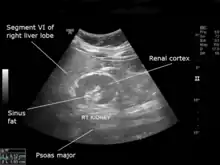

An ultrasound scan of a hypoplastic right kidney in an adult male.